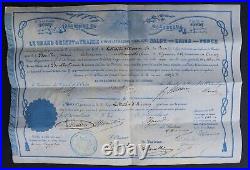

Ecole de Pharmacie de Paris (1836) : Diplôme de pharmacien 1836. La création et l’organisation de l’Ecole de Pharmacie de Paris datent de la loi du 11 avril 1803 et du décret du 8 octobre de la même année. De sa création en 1803. À son rattachement à l’Université en 1840, aucun acte législatif ou règlementaire majeur ne vient modifier la situation de l’école. En 1803 comme en 1836, date de ce document, des professeurs de l’Ecole de Médecine de Paris siègent dans les jurys d’examen. Ceci explique que ce diplôme soit délivré par les «. Professeurs à l’Ecole de Pharmacie de Paris, et Professeurs à l’école de médecine de la même Ville. Pour l’Ecole de Médecine. Médecin et chimiste espagnol, naturalisé français en 1818, il est un pionnier de la toxicologie médico-légale. Il signe ce document deux fois. La première en qualité de professeur, depuis 1819, à la faculté de médecine de Paris. La seconde comme doyen (1831 à 1848) de cette même école. Depuis 1834, il est également membre du Conseil royal de l’Instruction publique. Reçu docteur en médecine en 1820, il devint aide naturaliste au Muséum d’Histoire naturelle en 1827. En 1831, il obtient la place de professeur d’histoire naturelle médicale à la Faculté de Médecine de Paris, reprenant ainsi la fonction de son père, le botaniste Louis Claude Richard (1754 -1821). Pour l’Ecole de Pharmacie. Reçu maître en pharmacie en 1787, il s’adonne ensuite à la chimie. Attaché comme pharmacien à la maison de l’empereur, il accompagne Napoléon Ier lors de ses campagnes en Autriche et en Prusse. Lors de la fondation en 1803 de l’école de pharmacie, il occupe la chaire de chimie. En 1829, il devint directeur-adjoint et en 1832 directeur. C’est à ce poste qu’il signe ce diplôme. Pharmacien et chimiste français. Il fait d’importantes recherches sur les alcaloïdes d’origine végétale et découvre avec Joseph Caventou la quinine et la strychnine. Figure éminente de la pharmacie et de la chimie, ses recherches mettent en évidence plusieurs principes actifs comme la caféine, la narcotine et surtout la codéine. Louis René Le Canu. Il fait notamment paraître plusieurs mémoire sur le sang, sujet qui ne cesse de l’occuper pendant toute la durée de sa carrière. Document su vélin (335 x 216) avec frontispice au coq et « caducée exotique ». Diplôme délivré à Paris le 2 février 1836 et attribué à Joseph Alexandre BLANCHART. Ce dernier, né en 1812 à Péruwelz en BELGIQUE d’un père pharmacien, bénéficie d’une dispense d’âge pour ses examens. Diplôme avec un pli dans le sens de la longueur et trois dans la largeur. Les produits proposés à la vente sont de nature, de poids et de tailles très hétérogènes. Le paiement est considéré comme « soldé » une fois que l’argent envoyé par l’acheteur a été déposé sur le compte du vendeur. Paiement en ligne par carte bancaire. Par virement national ou international.